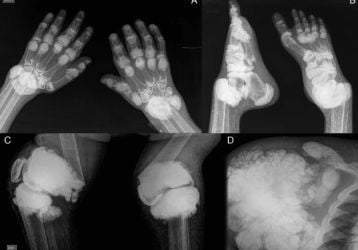

Лечение отложения солей в стопе: причины, лечение и профилактика

Почему происходит отложение солей в стопе. Медикаментозное лечение, физиотерапия и народные методы лечения. Рецепты для домашнего лечения.